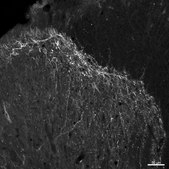

Immunohistochemistry Analysis: A 1:500 dilution from a representative lot detected substance P receptor in rat brain tissue sections.